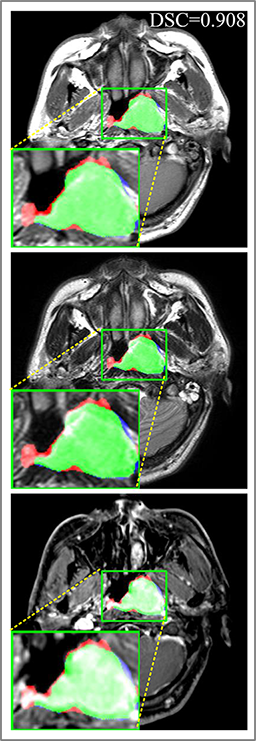

Comparison with ground truth. Some predicted results of MMFNet are shown in 2D images and 3D images in Figure 7 and Figure 8. As shown in these figures, although the shape and size of NPC are varied from each other, MMFNet can still accurately determine the regions of NPC and obtain the accurate contours of tumors. Through analyzing 2D images in figure 7, MMFNet has a capacity to fuse multi-modality MRI to reduce the confusion brought by intensity’ similarity between nearby tissues and NPC. The values of , and of MMFNet are shown in Table 1. MMFNet can reach the best results with , and .

Comparison with related works. Table 1 reports the values of , and for different methods. Predicted masks of different methods are illustrated in Figure 9 and Figure 10, which respectively present results in 2D and 3D images. Through comprehensively analyzing these results, the proposed MMFNet actually have the following properties:

(iii) It uses a fusion block to fuse low-level features from different modalities of MRI and prepare these low-level features for the fusion with high-level features. Thus, it can more effectively fuse information from various sources. It also uses the self-transfer strategy to initialize the netwerk. Hereby, it can stimulate encoders to make full mining of meaningful features from modality-specific MRI. And it finally improve base multi-encoder-based network (Merging encoders’ fetures) by , and in and .

Some typical predicted results of MMFNet are visualized in Figure 12. And it is worth mentioning that our proposed network is extremely time-friendly compared to manually marking by radiologists. Specifically speaking, our proposed method only needs about 9s to realize NPC delineation of a patient, while an experienced radiologist needs 10 to 20 minutes to complete it.